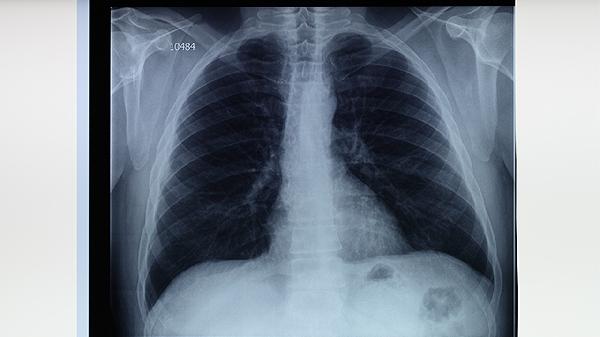

3、病情进展

胸部CT显示原有空洞扩大或新发浸润灶,可能伴随胸膜增厚或支气管扩张。广泛耐药结核病易导致双肺多叶受累,部分患者会出现氧分压降低等呼吸功能受损表现。此时需考虑使用注射用阿米卡星等静脉给药方案。